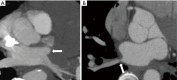

Acquired pulmonary vein stenosis (PVS) is an uncommon occurrence in adults, but one that carries significant morbidity/mortality. PVS can be secondary to neoplastic infiltration/extrinsic compression, non-neoplastic infiltration/extrinsic compression, or iatrogenic intervention. This article: (I) reviews the common causes of acquired PVS; (II) illustrates direct and indirect cross-sectional imaging findings in acquired PVS (in order to avoid misinterpretation of these imaging findings); and (III) details the role of imaging before and after the treatment of acquired PVS.